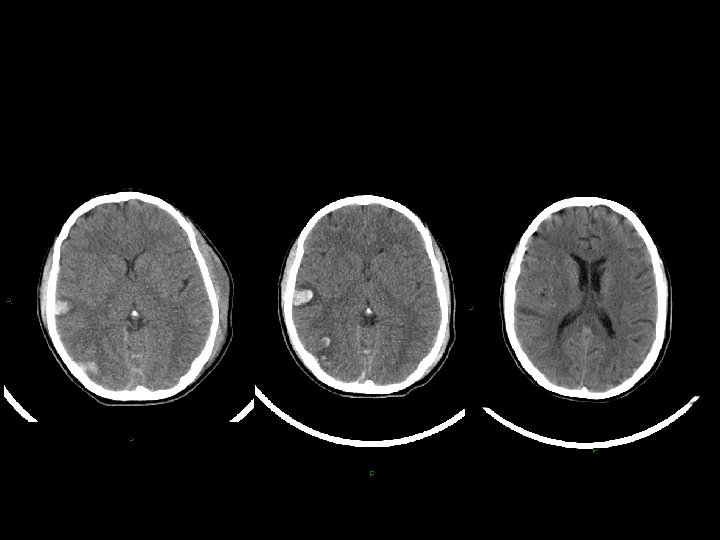

Stato vegetativo • giace, apparentemente incosciente, anche ad occhi aperti; • presenta funzioni cardiocircolatorie e respiratorie, termoregolazione, funzioni renali e gastrointestinali conservate; • non necessita di tecnologie di supporto; • mostra, alla TC e alla RMN, segni più o meno marcati di danno focale o diffuso; • presenta alla SPECT gradi variabili di riduzione sovratentoriali di perfusione cerebrale; • evidenzia, alla PET, variabile topografia e gradi variabili di riduzione del metabolismo del glucosio; • mostra alterazioni variabili dell’attività EEG.